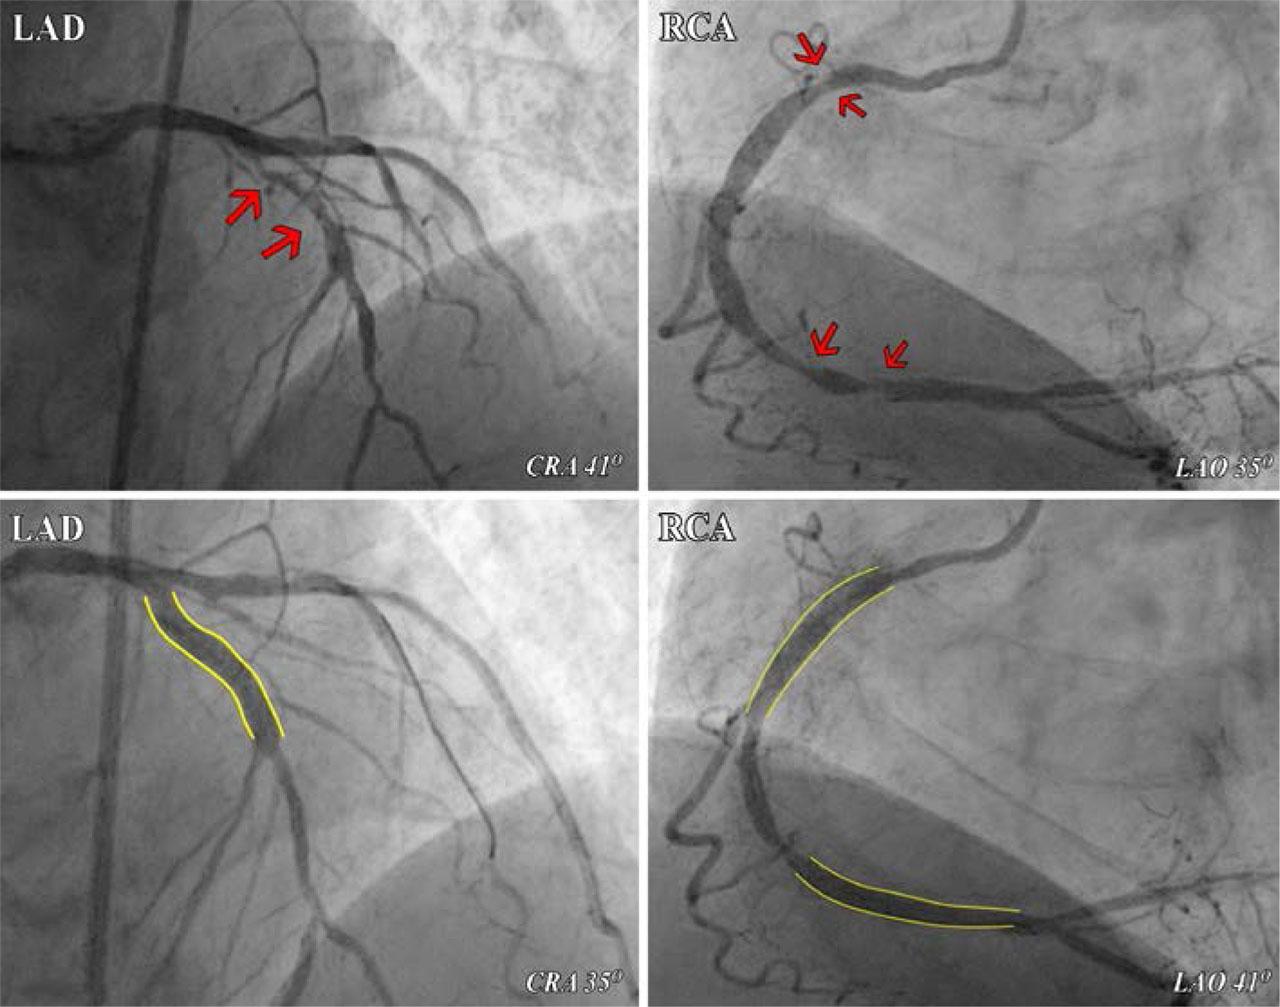

FIGURE 2.